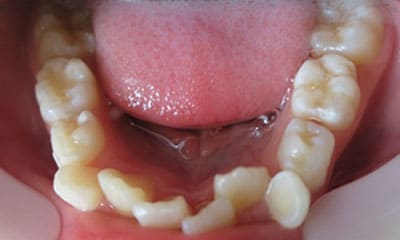

● 歯根が折れ保存不可の歯を抜歯して、そのスペースに八重歯を並べた症例

藤沢デンタルオフィスの虫歯や破折で抜歯後の部分矯正